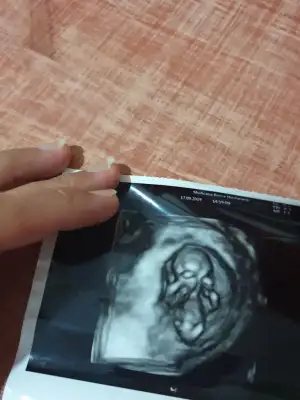

Maşallah suphanallahİnşallahbenim de 2 oglandan sonra rabbim ikiz kız nasip etti

Başka usg varsa tahmin edeyim nub görünmüyorKizlar Merhaba. Ikra meyra özellikle sana Merhaba canım. 10+5 olduk. Bugün kontrolum vardi cinsiyet için erken dedi bir tahminde bulunMadi. Sizin tahminlerinizi alayım birde :)

Evet kız minnoşBu da ablamın ultrasonu 12 haftalık doktor kıza benzettim ama saklıyo şuan demiş sizlerden yorum bekliyorum burdski yorumlae bazen doktordan daha kesin oluyo

Kızlar benim ufaklığın görüntüleri de bunlar, tahmin yürütebilir misiniz?11 hafta 5 günlük

selam kızlar, 12. haftada benim doktor nub teorisine ve ikili teste göre kıza benziyor demişti ama bacak arasında çıkıntı vardı ultrason görüntülerinde, bunun bazen kız bebeklerde klitoris olabileceğini söyledi. simdi 14+3 günlük olduk, dün ki kontrolde de erkek olduğunu söyledi. pek güvenemiyorum bu söylemlerden sonra sizce erkek mi kız mı bebişim:)